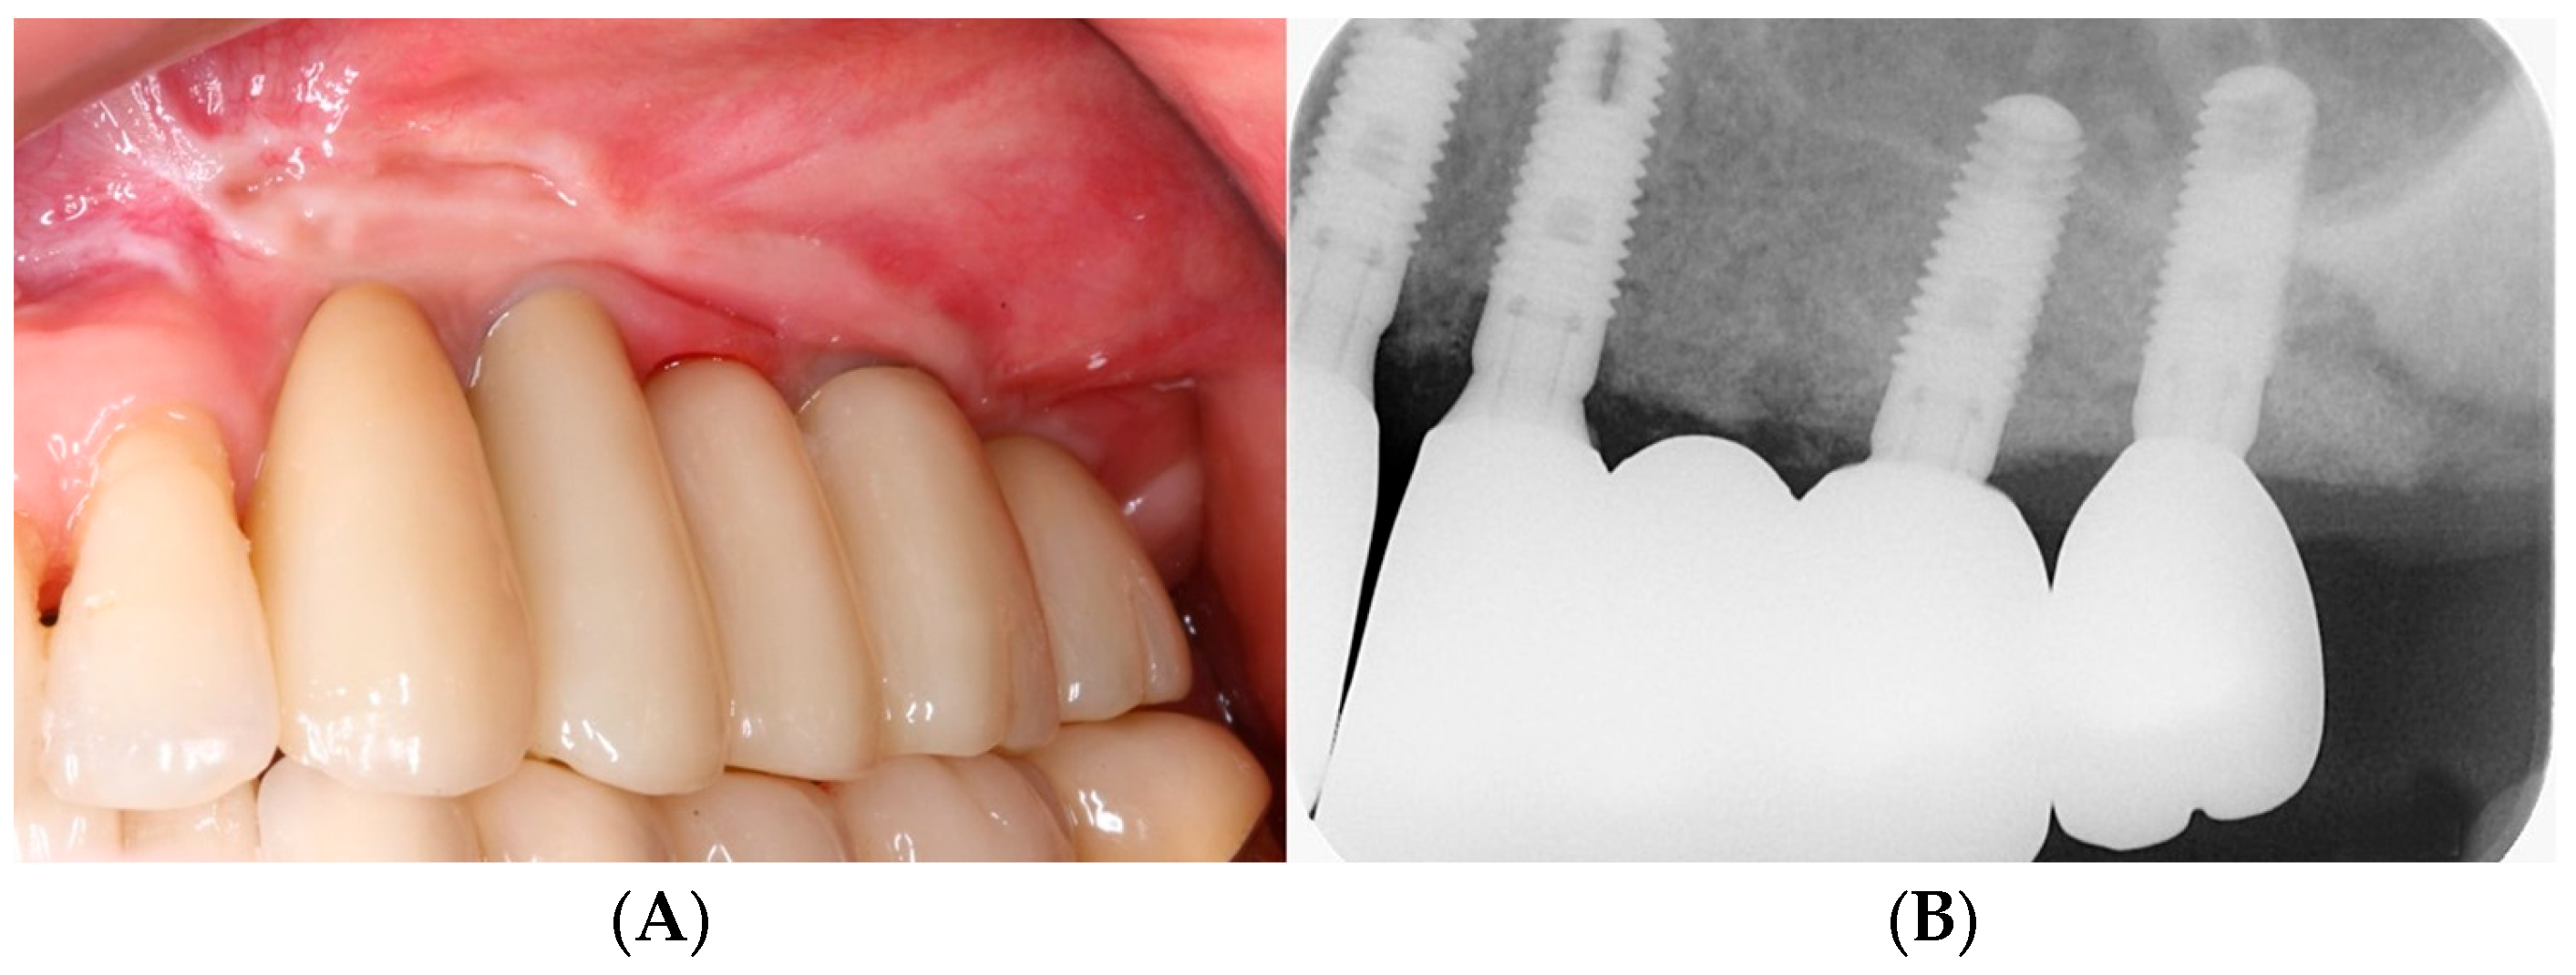

3.1. Clinical Results

3.2. Radiographic Results